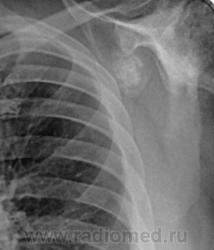

Снимки плечевых суставов.

Foto010.jpgFoto011.jpgFoto012.jpgFoto013.jpg

Уважаемый Александр, приходиться признать, что на цифровой рентгенограмме легких изменения плечевых суставов видны лучше, чем на "обрезаных" и недоэкспонированых снимках суставов. По имеющимся данным могу только сказать, что деф. артроз с кистовидной перестройкой структуры есть. Под хрящевой опухолью (возможно - хондросаркома) левой лопатки я имела в виду тень, отмеченую красными стрелками, которая в поле снимка не вошла. Моя вина - в силу специфики работы такие узкоформатные снимки давно были вредными, т.к. очень часто патология остается за пределами снимка. Остается рекомендовать рентгенография левой лопатки в прямой передне-задней и косой проекциях, а лучше - КТ...